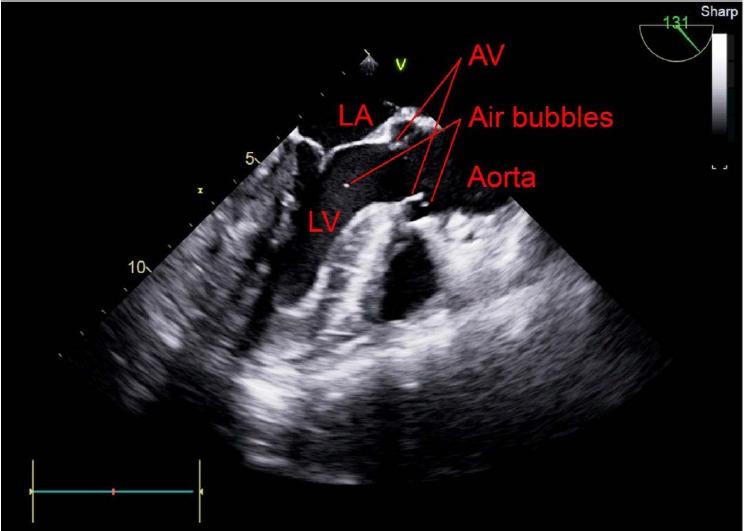

A 70-year-old male with hepatic cell carcinoma underwent laparoscopic hepatectomy. Though his vital signs were stable during the initiation of surgery, they became unstable during the procedure. The surgeon detected portal vein rupture, and transesophageal echocardiography was subsequently performed. A large amount of gas in the heart chamber and paradoxical embolism through a patent foramen ovale due to a right-to-left shunt were observed. We treated the symptoms, and the surgery was completed without any further issues.